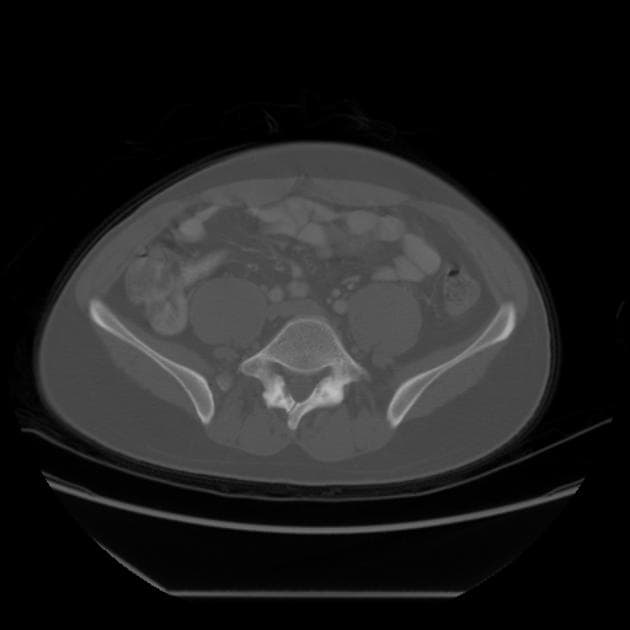

Series (6)

Transverse

- Khuyết tật ở vùng thắt lưng của tủy sống (defect in the lumbar region of the spinal cord)

Chẩn đoán NTD được xác nhận bằng cách khảo sát hệ thống từng cung thần kinh theo hướng đầu – đuôi (crania-caudal) trên mặt phẳng dọc và ngang. Trên mặt phẳng ngang, cung thần kinh bình thường có hình tròn kín, được da che phủ đầy đủ. Trong NTD, cung thần kinh có dạng hình chữ “U”, có thể kèm theo phồng lên: nếu có màng mỏng bao bọc là thoát vị màng não (meningocele), nếu trong khối phồng có chứa tổ chức thần kinh là thoát vị màng não tủy (meningomyelocele). Chiều dài khuyết tật được đánh giá trên mặt phẳng dọc 5.